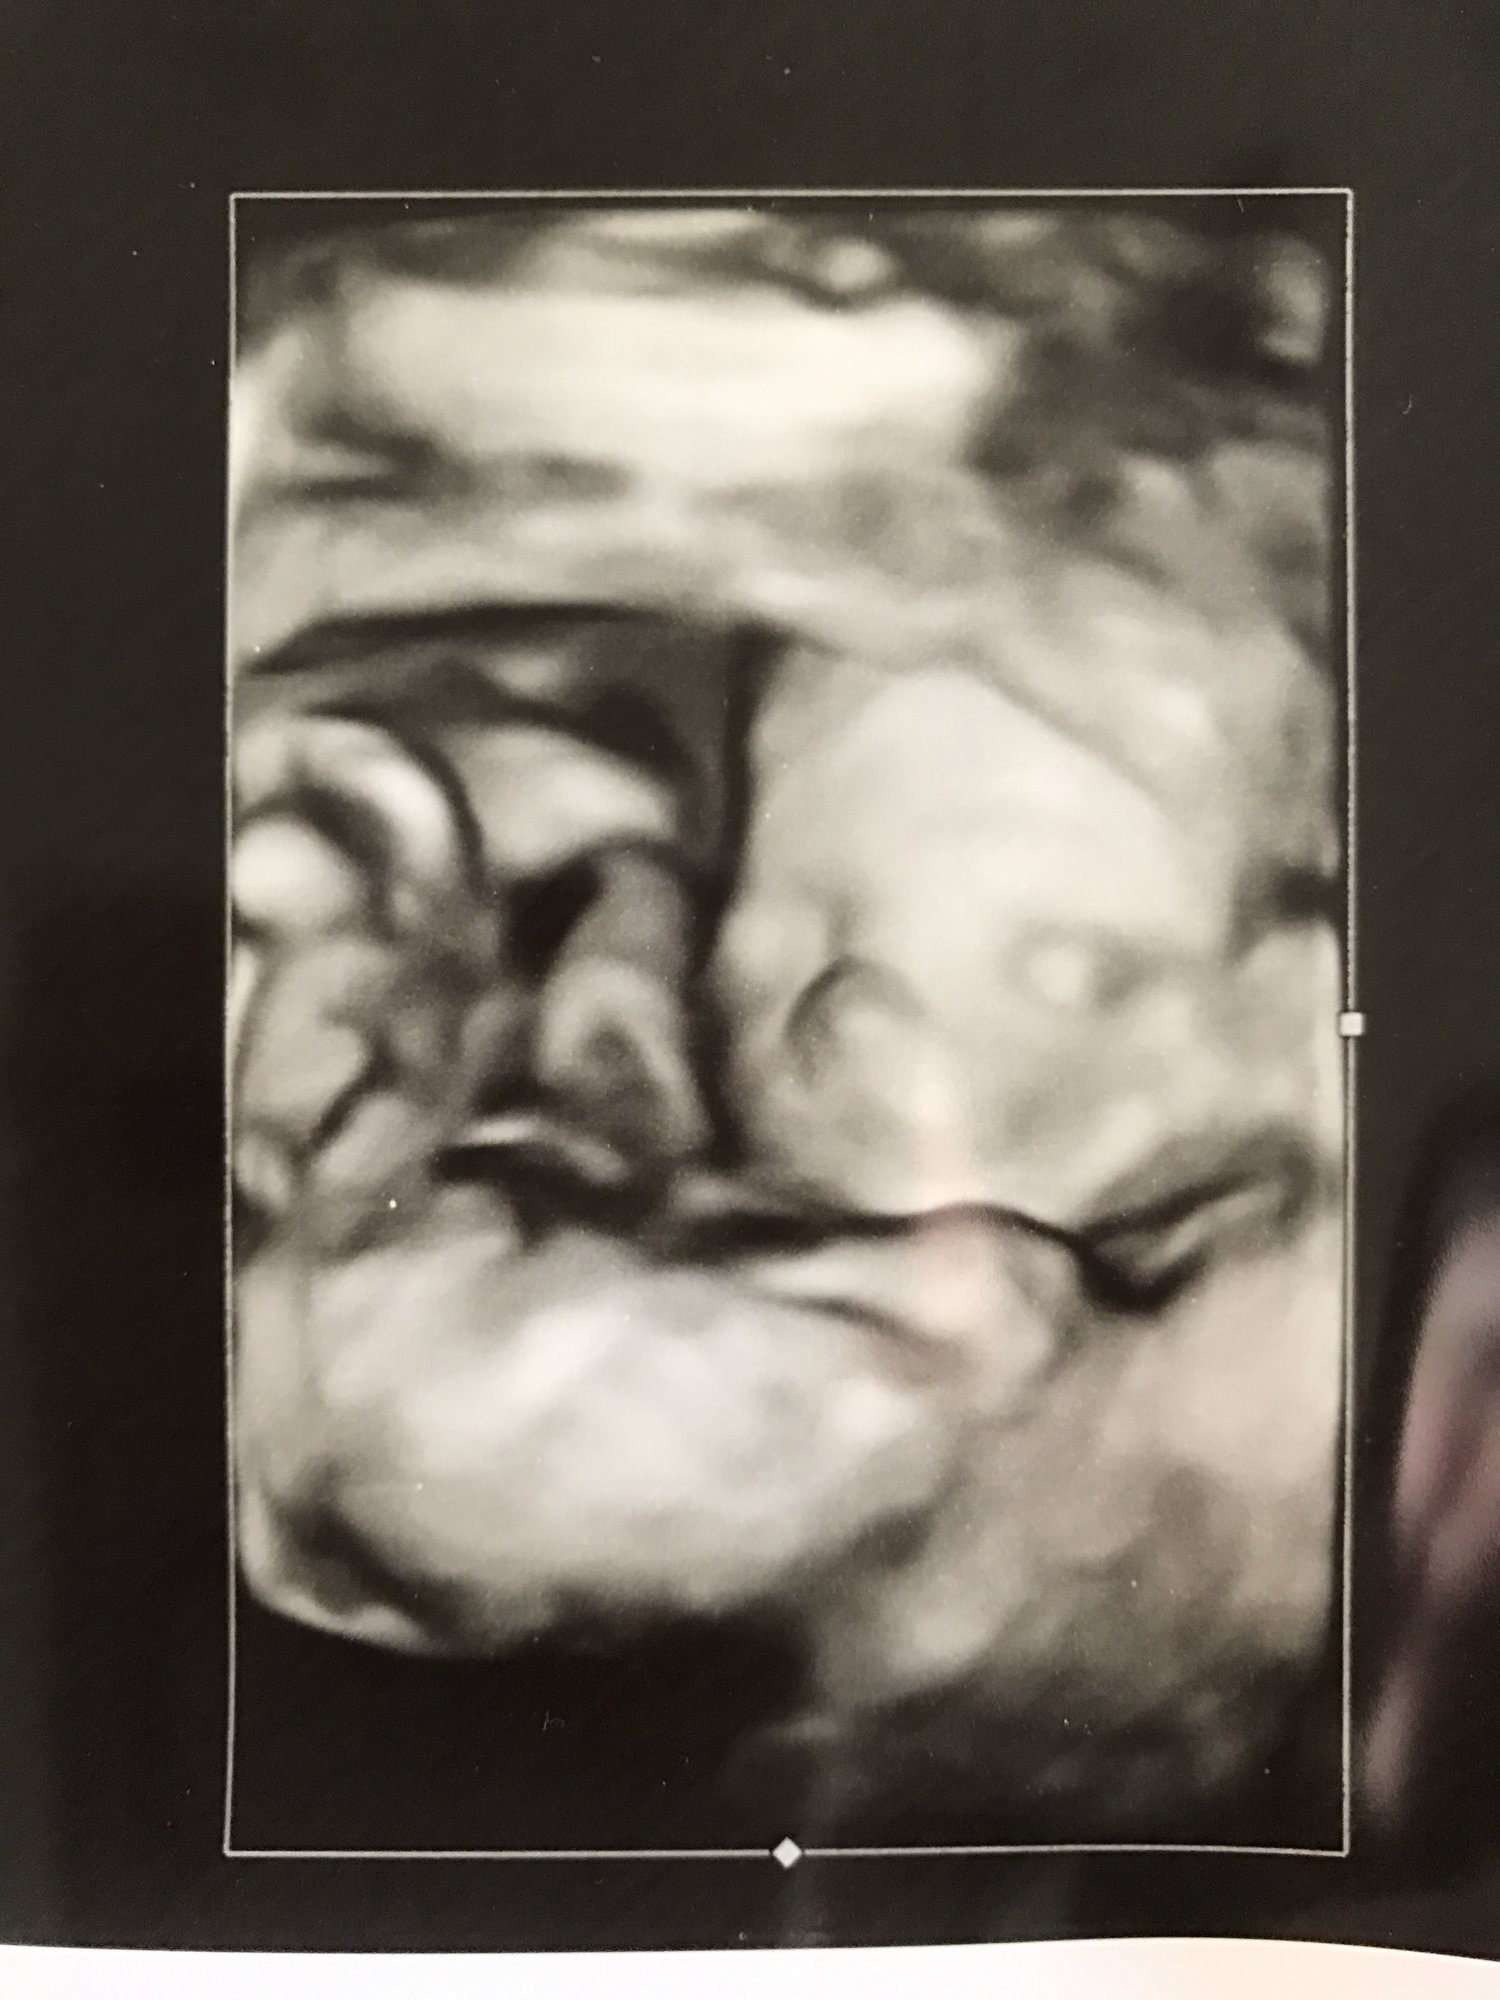

today we had our anatomy scan.... 19w! here's a little comparison between the NT Scan photo and today's Anatomy Scan photo!!! I love our little sweet pea so much!!!

here's a little comparison between the NT Scan photo and today's Anatomy Scan photo!!! I love our little sweet pea so much!!!